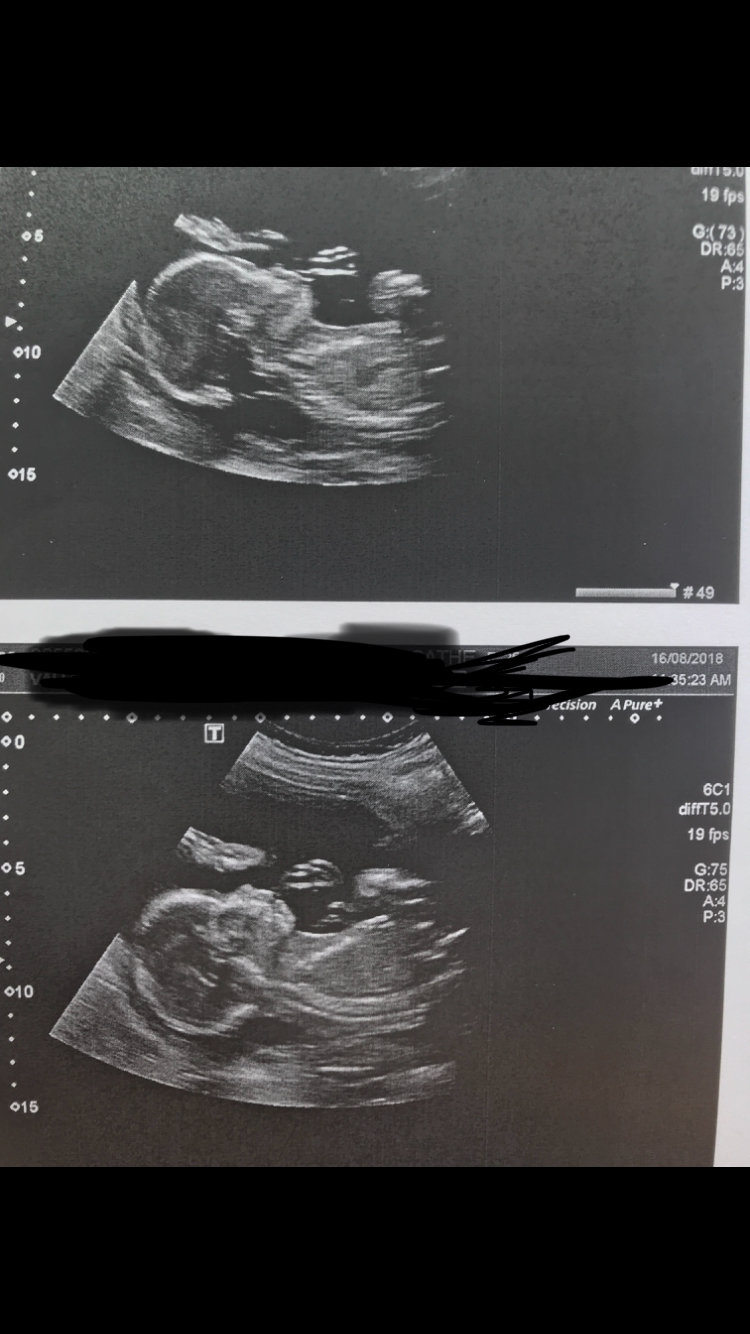

20 week scan, babies neck looks abnormally large.

Does it look normal?

• Babies always look weird in u/s. If the U/S tech & dr weren't concerned about the measurements then don't stress, they are all smushed in there so they are going to look disproportionate.

If there was a worry, the ultrasound tech would have either gotten a doctor to talk to you or will be on report findings and your doctor will talk to you at your next appointment.

Nothing looks "normal" on an ultrasound.  Would you look normal if you were smushed into a tight area? Nope!